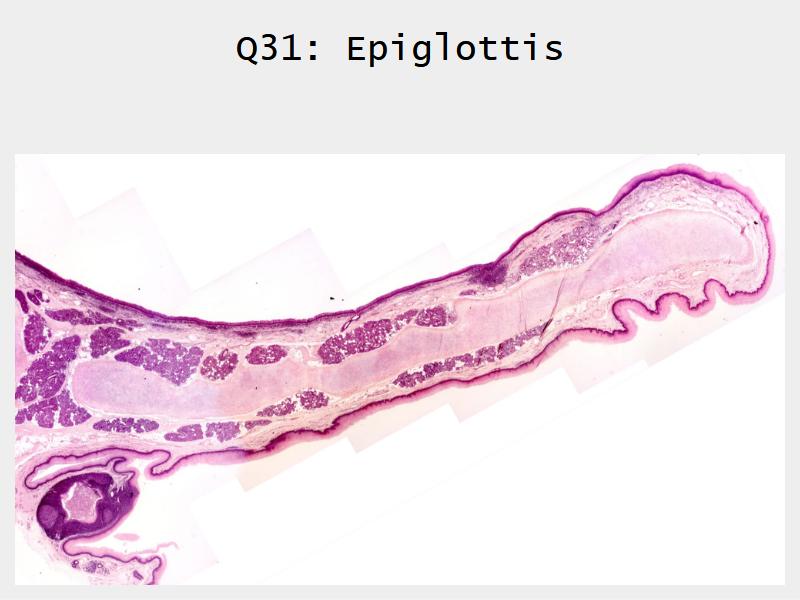

- Slide 111: Epiglottis

Epiglottis